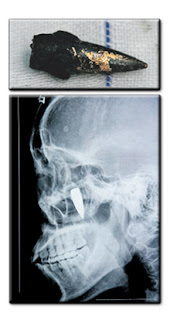

CHONGQIN - Seorang pesara di China, He Wenying akhirnya lega selepas sebutir peluru yang tertanam di dalam kepalanya sejak 42 tahun lalu akhirnya berjaya dikeluarkan, lapor sebuah akhbar semalam.

Peluru berukuran 3.3 sentimeter panjang itu berada di antara telinga dan rahang wanita berkenaan ketika berlakunya Revolusi Budaya di China pada 1967.

Ketika itu, sebutir peluru sesat mengenai Wenying apabila askar-askar komunis bertempur dengan kumpulan penentang.

Pesara berkenaan yang kini berusia 65 tahun mengadu mengalami sakit kepala sejak itu tetapi hanya menyedari terdapat peluru pada kepalanya apabila dia mendapatkan rawatan di sebuah hospital berhampiran pada 1978 kerana sakit kepala.

RUPA bentuk peluru yang tertanam di kepala Wenying.

Gambar X-ray menunjukkan sebutir peluru

yang tertanam di bahagian depan kepalanya

.

Selama tiga dekad sakit kepala wanita itu datang dan pergi namun dia hanya mengambil keputusan untuk mendapatkan rawatan selepas kesakitan merebak ke seluruh badannya.

Peluru tersebut akhirnya berjaya dikeluarkan beberapa orang doktor dan Wenying kini semakin sembuh dan dibenarkan pulang ke kediamannya. - Agensi